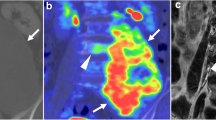

Fluoromisonidazole positron emission tomography (FMISO-PET) is used in delineating areas of hypoxia in tumours [63]. Hypoxic areas in tumours are generally difficult to treat, as these areas are generally radioresistant and show increased resistance to cytotoxic chemotherapy [64]. The knowledge of hypoxic areas can be used in radiotherapy dose painting with boost volumes on these hypoxic areas. The feasibility of FMISO-PET-CT-guided radiotherapy with hypoxia-directed intensity modulated radiotherapy has been demonstrated in multiple tumours [63, 65, 66], including head and neck cancer [67]. Cheney et al. [68] showed that hypoxic areas could be identified with FMISO-PET-CT in 12 out of 20 chordoma of the mobile or sacrococcygeal spine. The benefits and risks of hypoxia-guided boost volumes in radiotherapy of chordoma still have to be investigated in the future.

Chondrosarcoma are the most difficult differential diagnosis of chordoma of the skull base, as these lesions have overlapping radiologic and histopathologic features [52]. Many previous studies have found no definite CT or MRI features that distinguish between chordoma and chondrosarcoma [38, 47, 52]. However, there are some features that favour one over the other. Chordoma typically originate in the clivus and are therefore generally located more centrally, whereas chondrosarcoma arise in the petroclival fissure and therefore occur more laterally. [38] Unfortunately, this is not a distinctive feature, as lateral skull base chordoma have also been described [94, 95]. On CT, chondrosarcoma may show a typical ‘ring-and-arc’ chondroid matrix mineralization [96]. Figure 4 shows typical imaging characteristics of a chondrosarcoma. Recent studies show that diffusion-weighted imaging may differentiate between chordoma and chondrosarcoma, with chondrosarcoma having a higher average apparent diffusion coefficient than chordoma [51•, 97, 98]. The use of DWI in chordoma imaging is further elaborated below in ‘prognostics and radiomics’.

Chondrosarcoma. Imaging of skull base chondrosarcoma arising from the left lateral clivus with extension to the clinoid process, cavernous sinus and intracranial extension and compression on the left temporal lobe. Computed tomography (a) shows bone destruction with hyperdense fragments in the tumour mass, which corresponds with the typical ‘rings-and-arcs’ seen in chondroid tumours like chondrosarcoma. T2-weighted imaging (b) shows a heterogenous, mostly hyperintense mass. T1-weighted imaging (c) shows a hypointense mass with heterogenous enhancement (d). Pathologic examination of the tumour mass concluded chondrosarcoma WHO grade 1